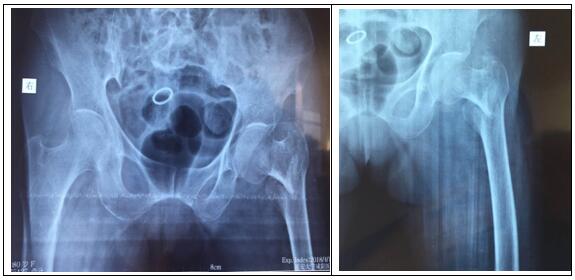

患者房某,80歲,女。因摔傷致左髖部疼痛,左下肢負重功能障礙,由外院轉入我院骨一科。確診為:左側股骨轉子間骨折。

圖片一:(術前照片)